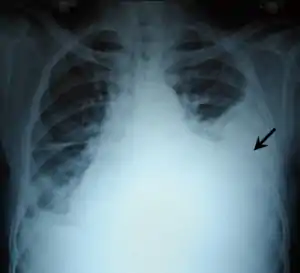

Chest X-ray showing left sided hemothorax (arrowed)

Chest X-ray

A chest X-ray is the most common technique used to diagnosis a hemothorax.[23] X-rays should ideally be taken in an upright position (an erect chest X-ray), but may be performed with the person lying on their back (supine) if an erect chest X-ray is not feasible. On an erect chest X-ray, a hemothorax is suggested by blunting of the costophrenic angle or partial or complete opacification of the affected half of the thorax. On a supine film the blood tends to layer in the pleural space, but can be appreciated as a haziness of one half of the thorax relative to the other.[5] A small hemothorax may be missed on a chest X-ray as several hundred milliliters of blood can be hidden by the diaphragm and abdominal viscera on an erect film. Supine X-rays are even less sensitive and as much as one liter of blood can be missed on a supine film.[24]